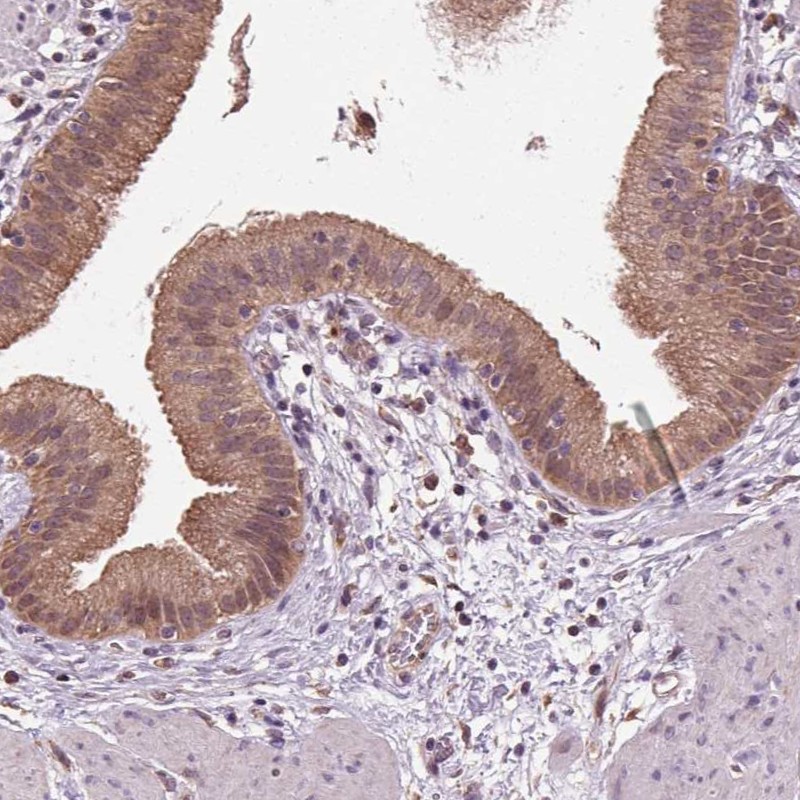

Immunohistochemical staining of human gallbladder shows moderate cytoplasmic positivity in glandular cells.